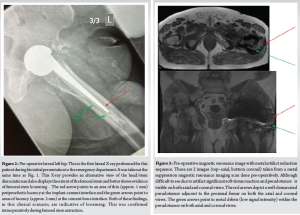

A 76 year old with a BMI of 36 kg/m2 male presented to the Emergency Department with left-sided hip pain and discomfort after performing a “twisting” motion of his hip while getting into bed. He described a “popping” sensation in his left hip upon doing this movement and immediately experienced a sharp pain and was unable to weight bear on that side. The patient described a discomfort in that left hip for the last 4 weeks before this acute presentation, which was not triggered by any trauma/injury. This patient had a MoM THA that was performed 16 years ago for osteoarthritis. He had had a successful outcome until now and denied any post-operative complications after the procedure. The MITCH TRH Modular head with an Exeter V40 cemented stem was used and the operation performed by an experienced consultant orthopedic surgeon. The patient’s medical history includes atrial fibrillation, coronary stenting, high BMI (36 kg/m2) hypertension, hypercholesterolemia, and bilateral total knee replacements. The patient is a non-smoker with occasional alcohol intake and mobilizes independently without walking aids at baseline. Clinical examination at the presentation revealed a shortened limb on the left side held in the neutral position. The patient was unable to straight leg raise due to pain and had a normal neurological and vascular examination. No visible signs of injury or trauma were present, and a systems examination was normal. The patient was admitted under the care of the orthopedic team, and investigations, including X-rays, MARS scan, laboratory tests (Full blood count, renal profile, C-reactive protein, coagulation profile, metal ion levels), and electrocardiogram, were ordered. X-rays (Figs. 1 and 2) revealed head-stem dissociation in a MoM hip configuration. Blood investigations were within normal levels and without any evidence of infection. Of note, metal ion levels are still in process. A MARS scan was conducted which revealed a subfascial 7cm × 7 cm × 10 cm collection posterior to the THA (Fig. 3.)